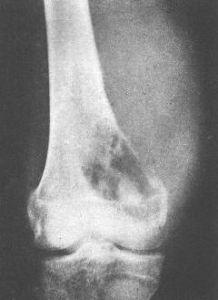

骨膜性软骨肉瘤是较少见的一种亚型,因其有独特的解剖和组织学特点,预后比中心性软骨肉瘤好,肿块多位于长骨的干骺端或骨干的一端,好发于股骨、胫骨和肱骨。临床症状主要为患处肿胀,伴轻度疼痛或无疼痛。治疗以手术切除为主,很少出现转移。